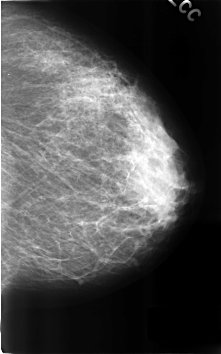

C_0313_1.LEFT_CC

LEFT_CC LINES 4600 PIXELS_PER_LINE 2872 BITS_PER_PIXEL 12 RESOLUTION 50 NON_OVERLAY